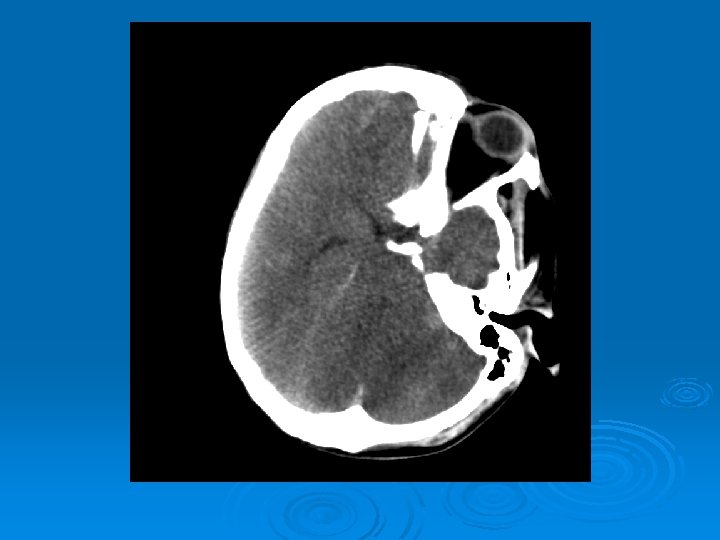

Course: Ø 3 PM, RN noticed anisocoria and L pupil non-reactive. Ø Neurology STAT dose mannitol and w/ dilantin. Ø Pt went for stat head Ct:

CT head 2/11/07 Ø A right frontal ventriculostomy catheter Ø Diffuse sulcal effacement with thickening of the cortex. Ø Loss of gray-white differentiation and hypodensity in the left parietooccipital region. Ø There is diffuse hypodensity of the cerebellum and brainstem. Ø Ø Ø The basilar cisterns are nearly completely effaced. Ø Impression: Ø Worsened diffuse cerebral edema The lateral ventricles are smaller

Course: Ø Neurosurgery saw pt: on exam she had lost cough, gag reflexes, corneal reflexes, she had flexed RUE, semipurposeful with bilateral extended LE. Ø Concern for herniation: placed Ø ICP 35 -40 10 th-11 th EVD